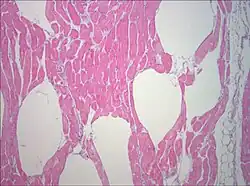

Muscle biopsy examined under the microscope (haematoxylin-eosin stain, zoom 100×): the large white areas between the muscle fibers are due to gas formation.

Muscle biopsy examined under the microscope (haematoxylin-eosin stain, zoom 100×): the large white areas between the muscle fibers are due to gas formation. -